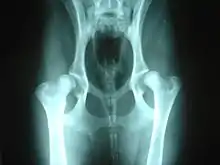

A number of conditions in dogs may be aggravated by or may show slow or no improvement as a result of weight bearing exercise. Among these are hip dysplasia and osteochondritis dissecans (OCD), conditions most common in medium to large purebred dogs, such as German Shepherds, Labrador Retrievers or Golden Retrievers; chronic degenerative radiculomyelopathy (CDRM), a degenerative disease of the spinal cord which causes hind limb problems in German Shepherds; and luxating patella which is seen predominantly in small and toy breeds.[2]